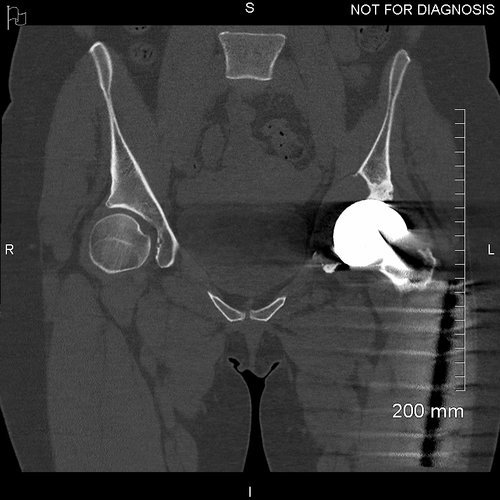

Coronal CT - This is used by the surgeon and the biomedical engineer to design the custom implant specifically to the patient’s acetabular bone stock. This CT demonstrates significant loss of bone stock relating to the left hip resurfacing.

3D CT reconstruction showing the hemipelvic defect.

Coronal CT showing that the acetabular component is properly seated and the screws are within the bone.